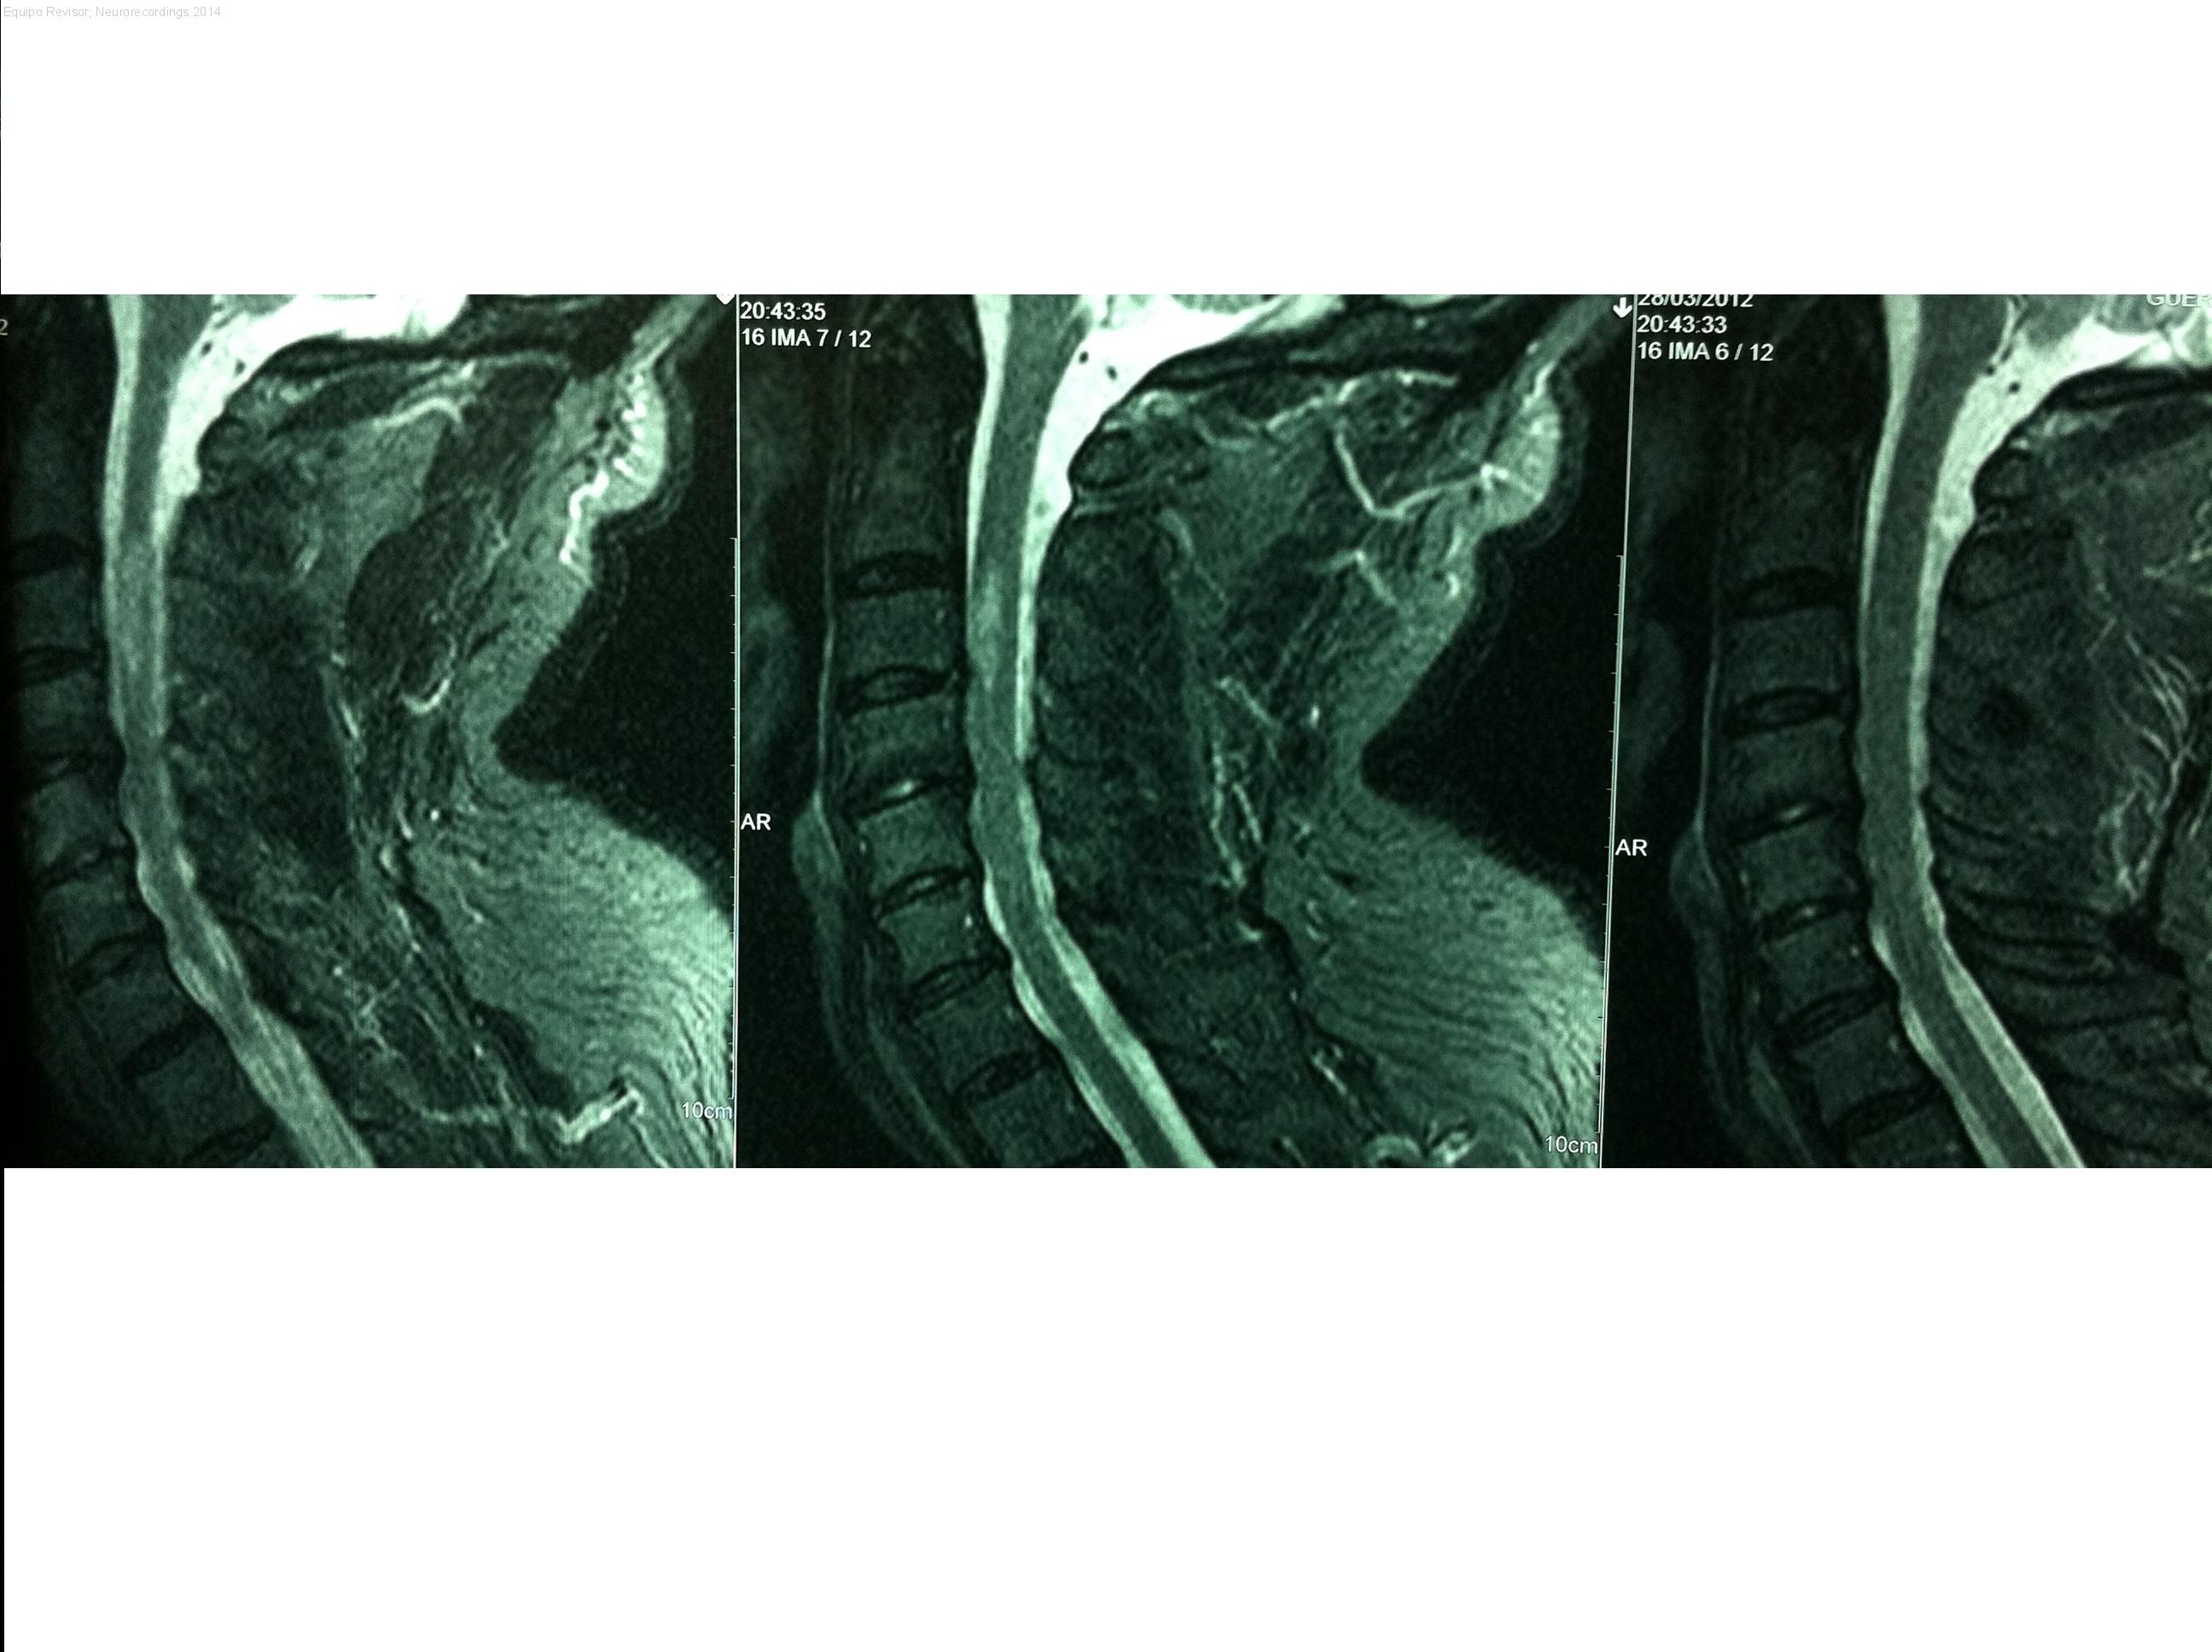

Diagnóstico final: Ictus isquémico medular. Ictus arteria espinal anterior